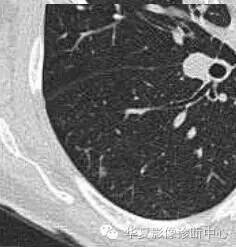

对于不好定的,不典型的一律建议抗炎后复查

如果不看边缘是否清楚,就好像癌肿

但是一看边缘就是炎性病变

大家记住了,边缘模糊的GGO首先考虑炎症